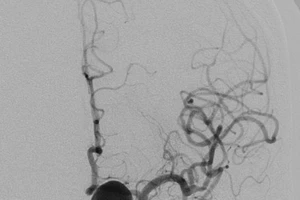

Kỹ thuật mới, cứu bệnh nhân có mạch máu não phình to suýt vỡ